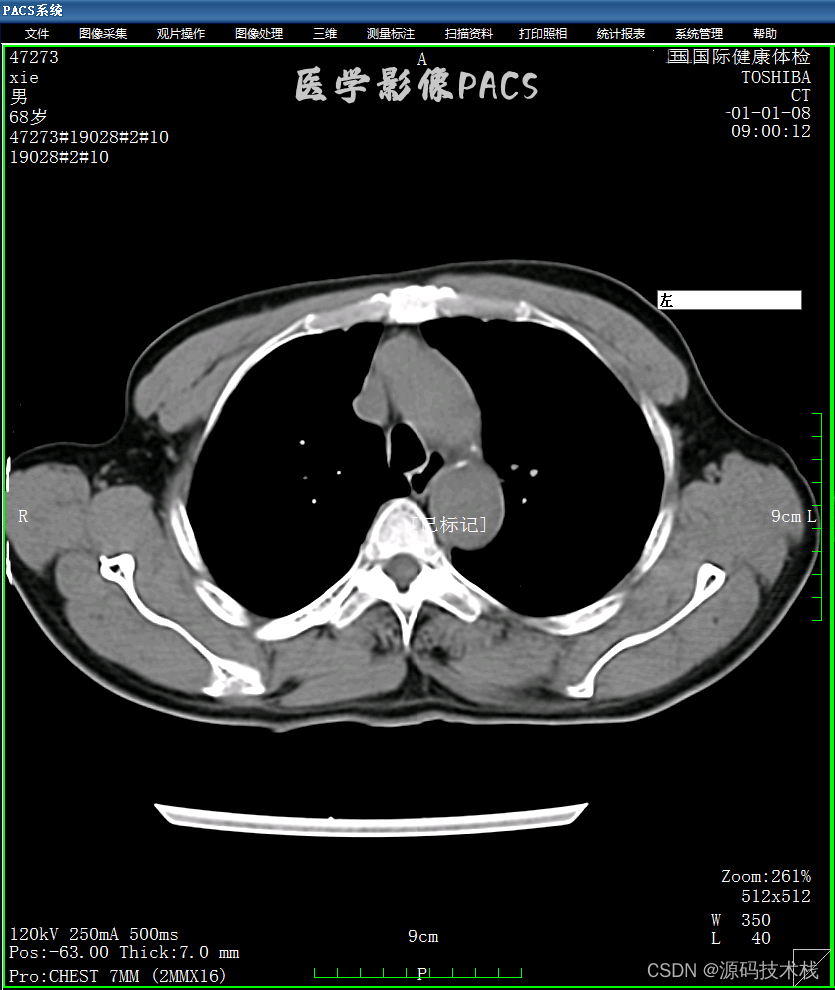

PACS系统适合卫生院、民营医院、二甲或以下公立医院的放射科、超声科使用。功能强大且简洁,性能优异,具备MPR(三维重建)、VR(容积重建)、胶片打印功能,能够快速部署。

PACS系统支持DR、CT、磁共振提供DICOM服务, 支持临床医生工作站提供报告和影像浏览服务,系统支持与HIS、体检融合,从对方服务器获取检查申请单,和推送结果,支持二次开发。

五、PACS功能介绍

(5)影像处理

·支持高清竖屏显示;

·窗宽窗位的预设和影像上鼠标拉拖方式连续调整窗口准位;

·提供定位图、定位线浏览模式;

·同屏分格显示病人不同体位、不同设备的影像,供诊断比较;

·影像漫游、无级缩放、局部放大;CT值坐标方式显示;

·提供图像标注,角度、面积等测量,支持骨密度测量;

·提供胶片打印功能,多种影像排列和影像组合方式输出。